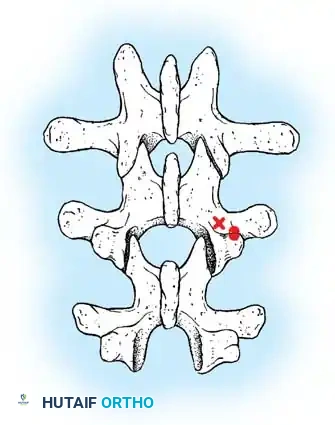

Lateral Exposure and Hemostasis

- Transverse Process Exposure: Extend the subperiosteal dissection laterally, first exposing the facet joints, and then continuing out to the tips of the transverse processes bilaterally.

- Segmental Vessels: As you dissect lateral to the facet joints, you will encounter the posterior branches of the segmental vessels. These must be meticulously identified and coagulated with bipolar or monopolar cautery to prevent insidious bleeding.

Fig. 38-24: Posterior view of segmental vessels located just lateral to each facet joint, requiring meticulous coagulation.

- Facet Cleaning: Use a sharp curet and a pituitary rongeur to completely excise the facet capsules and clean the interspinous ligaments.

Clinical Pearl: Always direct your curet from the midline laterally when cleaning the facet joints. This directional force ensures that if the instrument slips, it moves safely away from the spinal canal, preventing catastrophic dural tears or iatrogenic spinal cord injury.